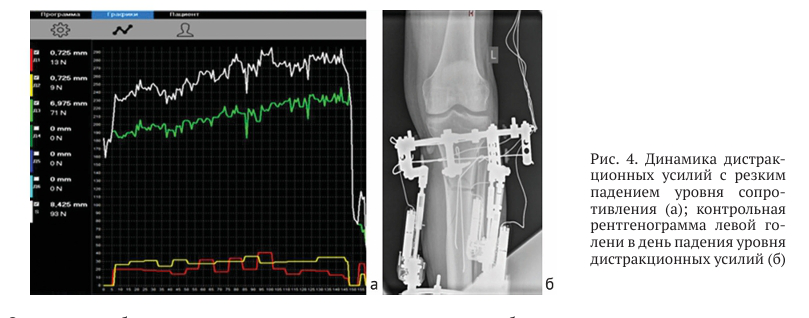

После операции установили три автоматических дистрактора (ведущий дистрактор — по внутренней поверхности голени, два ведомых дистрактора — по передне-наружной и задне-наружной поверхностям голени) таким образом, чтобы их шарнирные соединения проецировались на уровне продолжения биссектрисы угла варусной деформации большеберцовой кости [23]. Дистракцию начали через семь дней после операции темпом 1 мм/сут по ведущему стержню (по 0,025 мм за 40 приемов в сутки). Больной постоянно ходил с костылями, наступая на оперированную ногу (рис. 2, в). а измерение дистракционных усилий показало, что после достижения уровня в 290Н произошло их резкое падение до 20Н, что свидетельствует о нарушение непосредственной связи между костными фрагментами (рис. 4).

На седьмые сутки дистракции (22.07.24) во время работы дистрактора пациент отметил щелчок, сопровождавшийся умеренной болью. Объективный осмотр врачом не обнаружил каких-либо нарушений в аппарате Илизарова

Опираясь на объективные клинические, рентгенологические и биомеханические данные, дистракция была прекращена на два дня, после чего вновь начата темпом 1 мм/сут с ежедневным контролем дистракционных усилий.